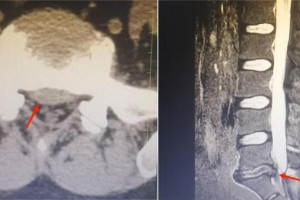

徐松 主任医师 硕士 骨外一科(脊柱、创伤骨科)副主任